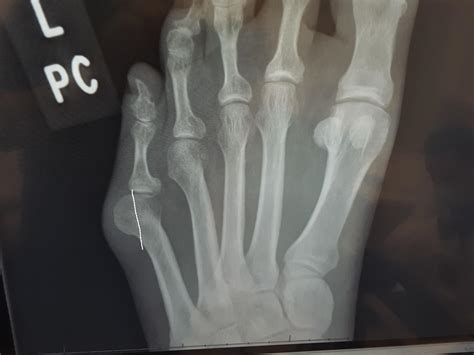

Bunions are bony bumps that form on the joint at the base of your big toe. They develop when the big toe pushes against the next toe, forcing the joint of the big toe to get bigger and stick out. This misalignment can cause pain, swelling, and difficulty wearing shoes. While conservative treatments like orthotics, padding, and pain medication can help manage symptoms, surgery may be necessary for severe cases.

Bunion surgery, also known as a bunionectomy, involves realigning the big toe joint and removing the bony bump. The specific procedure can vary depending on the severity of the bunion and the surgeon's approach. Common techniques include:

• Osteotomy: Cutting and realigning the bone.

• Exostectomy: Removing the bony bump.

• Soft tissue repair: Releasing or tightening tendons and ligaments.